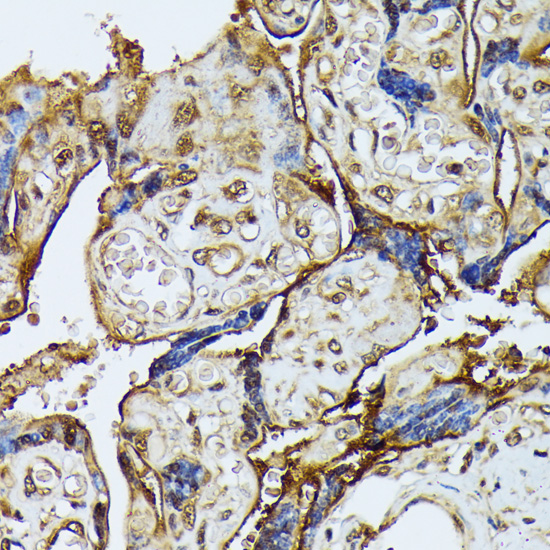

Immunohistochemistry of paraffin-embedded human placenta using DAPK3 antibody at dilution of 1:100 .